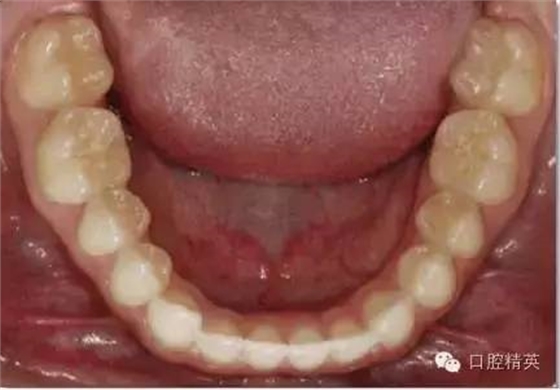

下颌合面照

合面观

1:2 (1:3) Mag nification

需要使用拉钩及反光板

•合面照需要使用成像清晰的反光镜。请拍摄时使用拉钩,否则软组织会包裹镜面阻挡牙面。

•中切牙唇面应位于相片边缘处。

•取景时应尽量减少反光镜边缘和嘴唇的暴露。患者的鼻子或非反光成像的牙齿应不要位于画面中。

•轻吹反光镜或将反光镜泡于温水中能减少镜面雾气的形成。

•相机应位于反光镜镜面45°左右处。反光镜中的成像应为牙齿的舌侧及唇侧都可见。一个过浅的拍照角会使得唇颊面及舌腭面的楔状隙角度记录有误。

•尽量暴露所有的牙齿。至少应包括从中切牙到第二磨牙近中。前牙应始终能清晰成像。

•照片中应能清晰显示下切牙边缘位置、唇颊侧及舌腭侧楔状隙。

•此照片可以从患者正前方拍摄(镜头稍向下斜,患者头部向后靠)。直接位于病人后方拍摄会非常困难。

•患者舌头应尽量避免遮挡牙面,应嘱患者尽量后缩舌头,或用反光镜子挡住舌头。

•焦点位于反光镜中的双尖牙。

•开始先使用1:2 (1:3)放大倍率,然后调整放大倍率以拍摄下颌牙弓作者:牙医加加